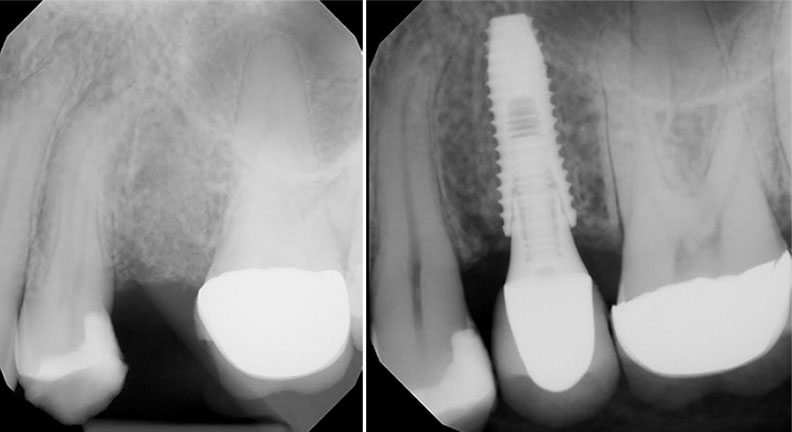

At Dental Group Palomar, we offer dental implants as a premier solution for replacing missing teeth. Dental implants are small titanium posts that are surgically placed into the jawbone beneath the gums, providing a strong and stable foundation for custom-made dental prostheses that look, feel, and function like your natural teeth. Whether you are missing a single tooth, multiple teeth, or need a full-mouth restoration, dental implants can help you achieve a confident and healthy smile.

Dental implants have an impressive success rate of 98%, making them a reliable and effective option for tooth replacement. If you’re considering dental implants, let the experienced team at Dental Group Palomar guide you through the process. We will work closely with you to create a customized treatment plan that meets your needs and restores your smile.